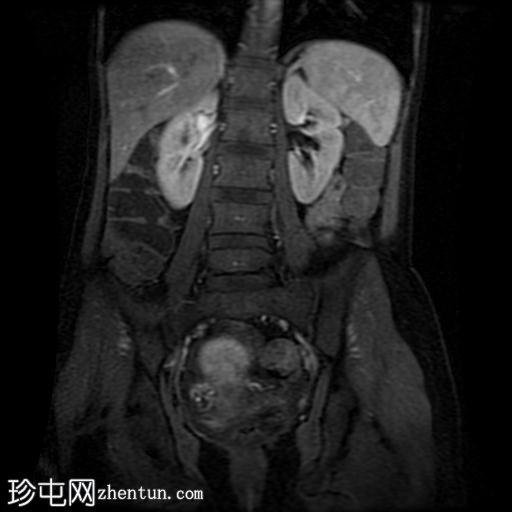

冠状位T1加权像

增强脂肪抑制

回肠末端及盆腔回肠肠袢可见长段肠壁增厚及强化,肠周血管丰富,呈“梳状征”,并可见明显的纤维脂肪浸润。

未见瘘管、积液、腹水或梗阻。

磁共振肠道造影(MRE)结果支持克罗恩病的诊断,显示远端及末端回肠以活动

性病

变为主,并可见明显的肠周血管。